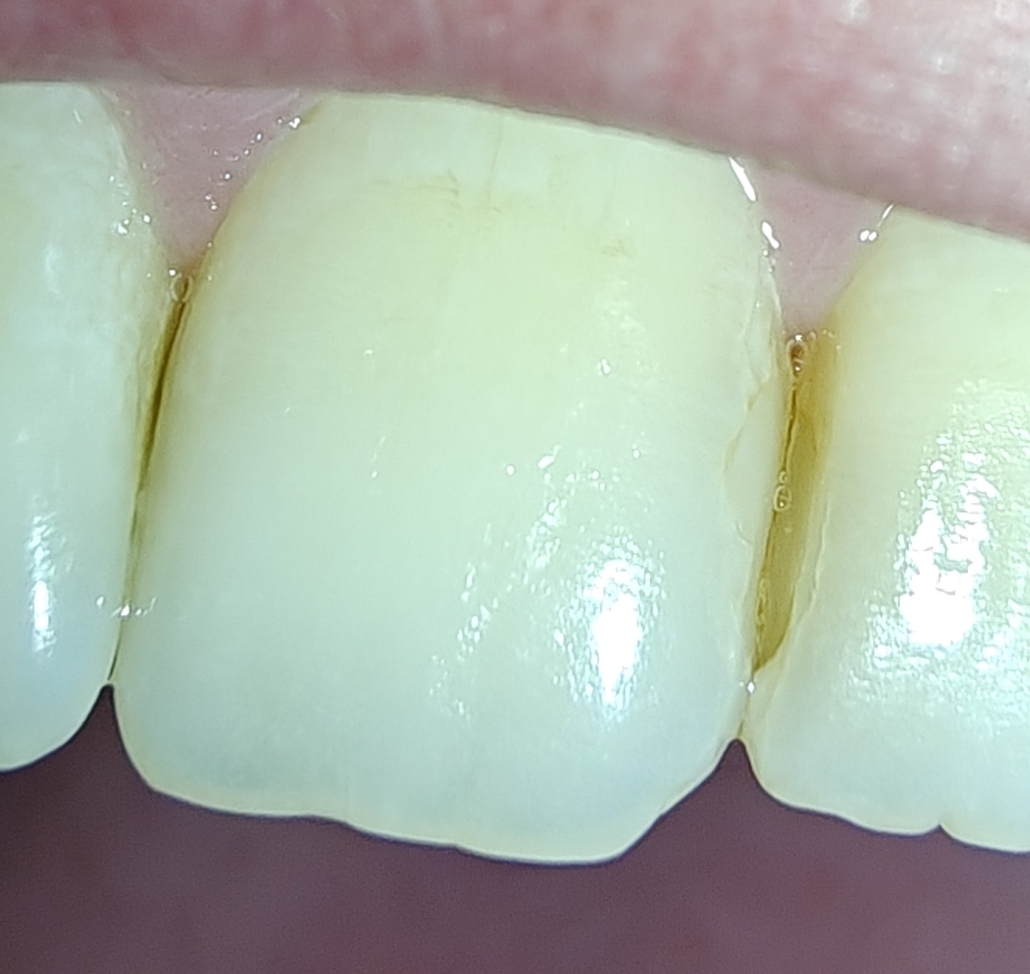

2 первых заебенил - 12к.

Я сегодня в первый раз лечил пульпит, советую! Поставят пломбу белую-белую, будет как снежинка в твоем желтом царстве (у меня так)